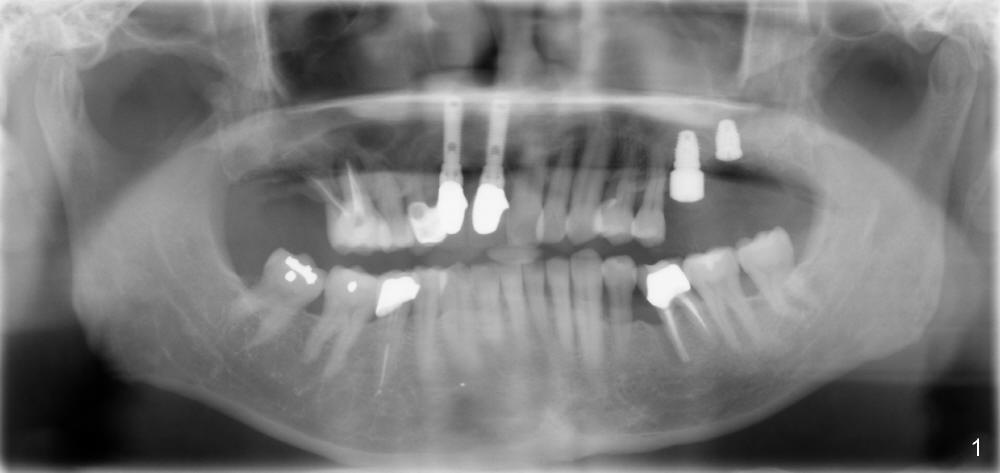

If the septum is basically intact, a 5.3x12 bone-level implant is placed in an ideal trajectory for restoration (Fig.3). The mesial and distal margin of the implant is at the level of the alveolar crests (arrows); bone graft is placed evenly to cover the coronal threads (red circles). If the septum is defective to some degree, a longer implant is placed distally (Fig.4) with more bone graft placed distally. Or the implant is placed deeper (Fig.5). If the septum is severely defective, an extra wide, but shorter implant (6.9x10 mm bone-level SM) is used (Fig.6). Or an extra wide UF implant with extra 2 mm length may offer better primary stability (Fig.6' (with sinus lift)). The primary stability of the extra wide implants is derived from contact with the mesial and distal socket walls.